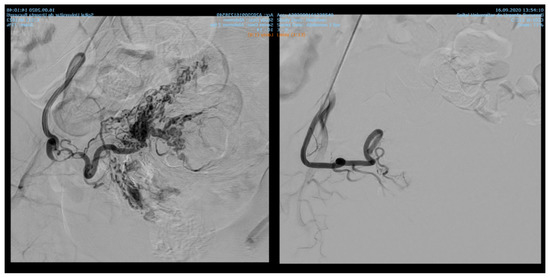

Among 1135 patients, 88.19% presented with uterine leiomyomas (n = 1001), where supra-selective uterine arteries embolization was used. Pre- and postprocedural aspects of uterine artery embolization in a patient with uterine leiomyomas are shown in Figure 1.

Figure 1. Uterine artery embolization in uterine leiomyoma.